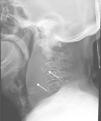

Se realiza radiografía lateral de columna cervical donde se objetiva fractura vertebral a nivel de porción anterior del cuerpo de la tercera vértebra cervical e importante hematoma prevertebral (fig. 1); hallazgos corroborados en el TAC cervical apreciándose como dicho hematoma comprime parcialmente la vía aérea (fig. 2).